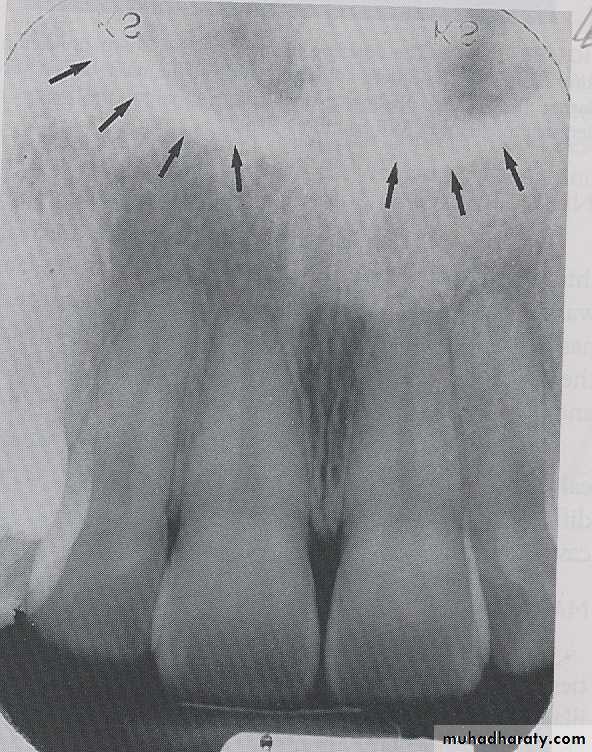

INCISIVE FORAMEN: The incisive foramen is an opening in the bone that is located at the midline of the anterior portion of hard palate. Radiographically the incisive foramen appears as a small ovoid or round radiolucent area located between root of maxillary central incisor.

The superior foramina of the incisive canal are two tiny openings or holes in bone that are located on the floor of the nasal cavity. The superior foramina are the openings of two small canals that extend downward and medially from the floor of the nasal cavity. These two small canals join together to form the incisive canal and share a common exit, the incisive foramen.Appearance. On a maxillary periapical image, the superior foramina appear as two small, round radiolucencies located superior to the apices of the maxillary central incisors

MEDIAN PALATEL SUTURE: The median palatal suture is the immovable joint between two palatine process of maxilla. Radiographically the suture appears as thin radiolucent line between the central incisor, the median palatal suture bounded in both side by dense cortical bone that appear radiopaque.